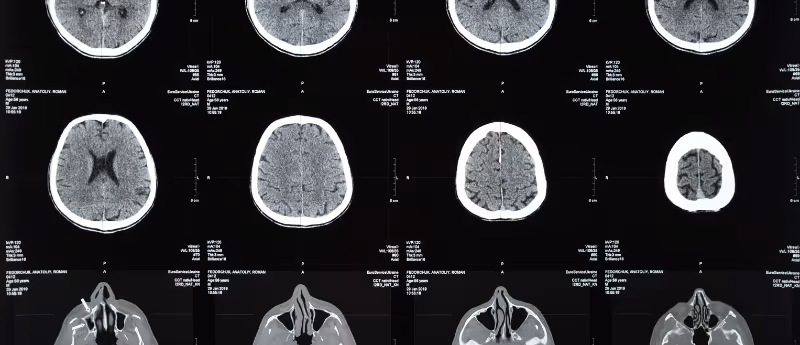

In this opinion piece, Andrea Isoni (AI Technologies; London, UK), author of Machine Learning for the Web, provides his outlook on why applications of AI in radiology have been lacking and his thoughts on how the field will evolve in the future. It was around 2018 when pressing news came that AI would soon be able to replace radiologists (mostly led by the publicized IBM Watson, but not solely). Doctors themselves dropped studying radiology as a specialization in mass. In this case, AI failed. And we may now have an actual shortage of radiologists. Today AI diagnostic accuracy scores are approximately 65%, compared to an 85% average for a radiologist . What happened? First, as outlined above, the accuracy is (rightfully) calculated based on diagnosis, not just images. A radiologist today provides a diagnosis not just based on the radiographic image alone, but based on data and the general condition of the patient, which are not really considered by the AI model. Second, both radiographic images and metadata are taken from different manufacturers, meaning they are not standardized and sometimes labels are not as strictly consistent as they should be. The AI model has been trained with heterogeneous data and unsurprisingly, the accuracy could therefore be questioned and improved upon. The case moving forwards Overtime, the second point above regarding accuracy will be solved. Maybe in 5 years, or maybe in 10. It would depend how quickly data can be standardized and become 'AI friendly': the ease at which radiographic images and their metadata can be uniformly ingested into AI training. Manufacturers may or may not have the right incentives to do so. The question remaining to be tackled: how can an AI model make a fully informed diagnosis by incorporating different sources of patient data together, including for example, data from physical examinations, and combining them with radiographic images? Combining these data sources may return various scenarios that may not have evenly distributed data, so the model cannot actually replace the radiologist. In other words, until we have standardized data of patients with good statistics for different cases (to cope with the variability of scenarios) it may be difficult for an AI model to perform as well as a human. My guess of the future In the next 5 years, if there is an economic incentive, it may be possible to make a specialized AI model just for certain diseases but not for general conditions (for example an AI model for cancers or broken bones). Radiologists will always be needed, and their jobs will just change over time, not disappear. A human today can ingest and generalize across non-standardized heterogeneous data, in a way that we need to still develop in AI. If we do manage to create this ability in AI, then AI radiologists might be around soon.